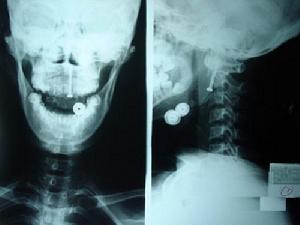

齒狀突和脊髓各占椎管矢狀X線檢查是診斷齒狀突骨折的主要依據和手段。當診斷有懷疑時,應反覆拍片,加攝斷層片或行CT檢查MRI檢查可提供脊髓損傷的情況在橫切面上,齒狀突和脊髓各占椎管矢狀徑的1/3,餘1/3為緩衝間隙(圖1)。成人寰椎前弓後緣與齒狀突之間距離(AO間距)為2mm~3mm,兒童略大為3mm~4mm,超出這一範圍即應考慮有齒狀突骨折和/或韌帶結構斷裂。開口位片上齒狀突兩側不對稱亦應懷疑該部位的損傷清晰的開口位片可以顯示齒狀突骨折及骨折類型側位片可顯示骨折類型及前或後的移位和是否有寰樞椎脫位。另須注意有無合併頸枕部其他部位的畸形和骨折。

樞椎齒狀突骨折X線片顯示的齒狀突骨折主要是骨質中斷、移位和成角,最可靠的指征是移位,有時開口位片上齒狀突側方成角是唯一的徵象。一個高質量的側位片在齒狀突骨折的診斷中是必需的,因齒狀突骨折常伴有前後移位和成角,且移位方向的信息對治療有指導意義。但偶爾齒狀突解剖突異,出現向後傾斜,應避免誤診為骨折。間接徵象如椎前軟組織陰影的價值可能僅局限於損傷的定位,且有時椎前軟組織是正常的,特別是傷後立即檢查的情況。另一方面有時頭面部骨折也可造成椎前軟組織腫脹。Ehara的50例患者,43例在一張最初的側位片上顯示骨折征,占86%3例在開口位上顯示齒狀突骨折,1例在頭顱側位片上發現齒狀突骨折僅有3例普通X線片陰性。斷層片上顯示齒狀突骨折主要是骨皮質的中斷和齒狀突基底部的陰影,矢狀面的斷層片可顯示齒狀基底部的陰影,矢狀面的斷層片可顯示齒狀突骨折移位和成角,對診斷非常有價值。Harris等描述了矢狀面投影上齒狀基底部一個環形陰影,顯示骨質中斷,是Ⅲ型齒狀突骨折的一個徵象。